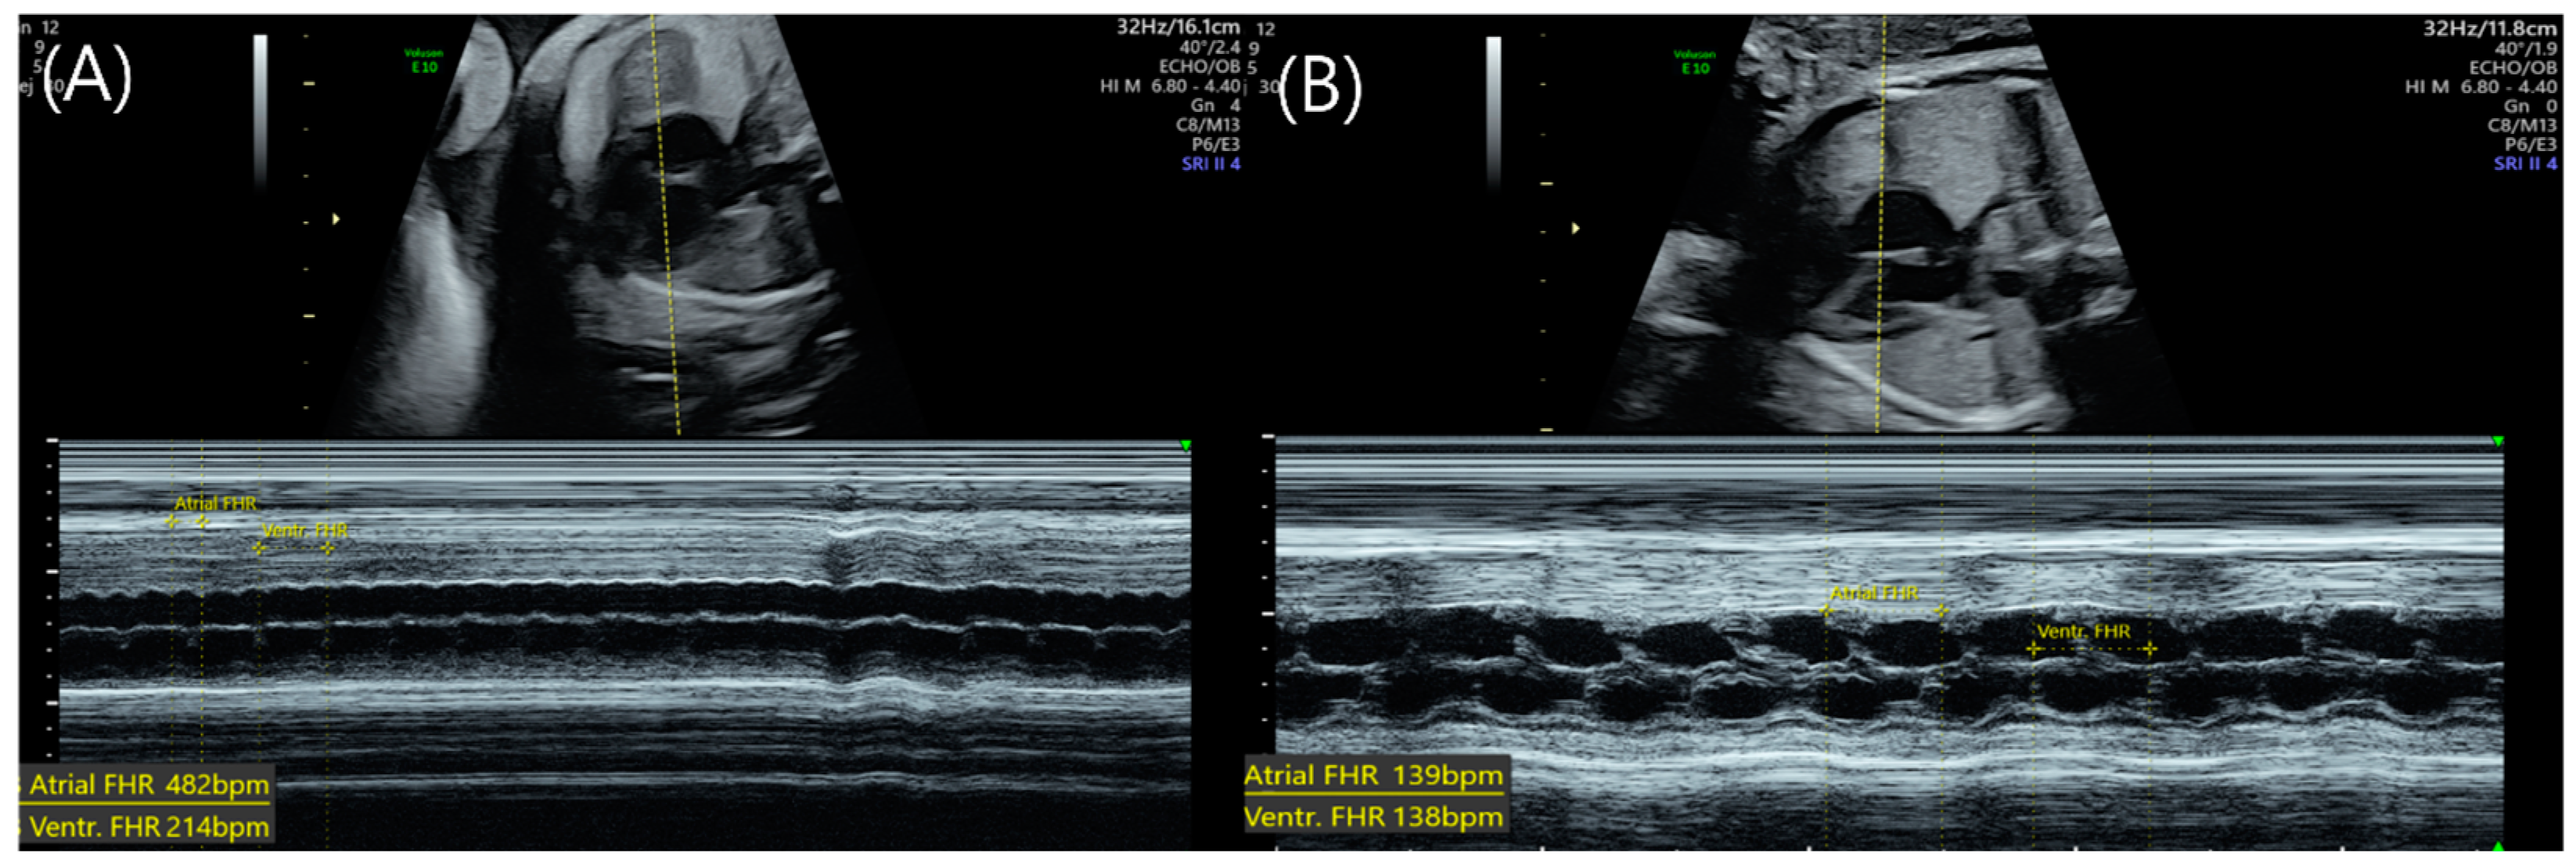

| Atrial flutter | Regular | 350–500 | 1:1, 2:1, 3:1, 4:1 | Variable depending on AV conduction |